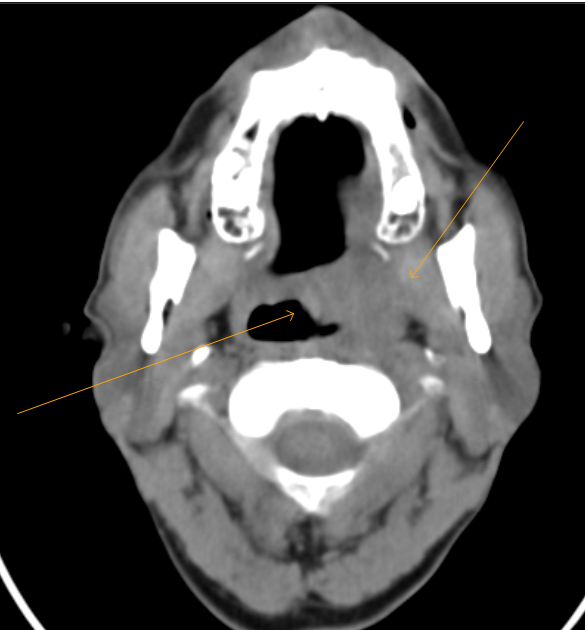

From www.researchgate.net

Initial CT scan with IV contrast of left palatine tonsillar mass before Tonsils Labeled Ct They collectively form a ringed arrangement, known as waldeyer’s ring: Scrollable ct highlighted the anatomy of the neck. Labeled and unlabelled images of a contrast ct of the neck. There are several ways to categorize this infection: 21 articles feature images from this case. The tonsils are collections of lymphatic tissue located within the pharynx. Learn about its anatomy, function,. Tonsils Labeled Ct.